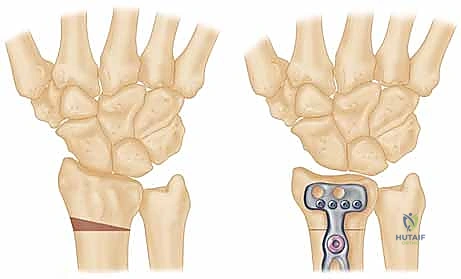

عملية تقصير عظم الكعبرة هي إجراء جراحي فعال لعلاج مرض كينبوك، وهو نخر لاوعائي يصيب العظم الهلالي في الرسغ. تهدف العملية إلى تخفيف الضغط عن العظم الهلالي وإعادة توزيع القوى داخل الرسغ، مما يقلل الألم ويوقف تطور المرض. يقدم الأستاذ الدكتور محمد هطيف في صنعاء هذه الجراحة بدقة عالية.

الخلاصة الطبية السريعة: عملية تقصير عظم الكعبرة هي إجراء جراحي دقيق وفعال يُستخدم بشكل رئيسي لعلاج "مرض كينبوك" (Kienböck's Disease)، وهو حالة من النخر اللاوعائي تصيب العظم الهلالي في مفصل الرسغ. تعتمد فكرة العملية على تقصير عظم الكعبرة بمقدار مليمترات قليلة لتخفيف الضغط الميكانيكي الهائل الواقع على العظم الهلالي، وإعادة توزيع القوى داخل الرسغ بشكل متوازن. يؤدي ذلك إلى تقليل الألم بشكل ملحوظ، إيقاف تدهور العظم، وتحفيز التروية الدموية. يُعد الأستاذ الدكتور محمد هطيف، أستاذ جراحة العظام والمفاصل بجامعة صنعاء واستشاري جراحات العظام الدقيقة، الخبير الأول في اليمن لإجراء هذه الجراحة المعقدة بأعلى نسب النجاح.

| تقصير عظم الكعبرة (Radial Shortening) | تقصير الكعبرة بمقدار 2-3 ملم لتخفيف الضغط عن العظم الهلالي وتوزيع الأحمال. | المراحل II و IIIA مع وجود تباين زندي سلبي. | ممتازة جداً، تخفف الألم وتوقف تطور المرض بشكل فعال. |